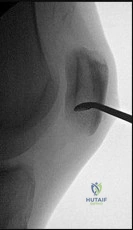

A 48-year-old male with end-stage post-traumatic ankle arthritis, severe subtalar arthritis, and a mild equinus contracture presents for surgical management. He is a non-smoker, has no diabetes, and desires to maintain some motion. Clinical examination reveals significant tibiotalar and subtalar stiffness with pain. Radiographs

confirm advanced arthritis in both joints. What is the most appropriate surgical recommendation?